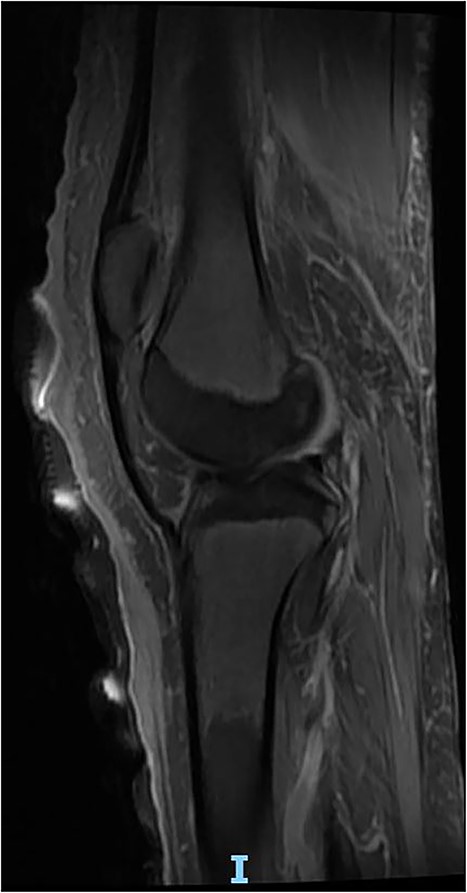

An 18-year-old girl, known case of DEB presented to the emergency department with 1 day history of right knee foreign body sensation, stabbing pain and multiple skin lesion noticed on the same day of presentation. On clinical examination, she had multiple areas of sloughed skin at right knee and leg with multiple furuncular lesions with visible moving larva (Fig. 1). Patient could not do any range of motion of the knee joint due to pain. She was immediately planned for emergency right knee exploration and extensive debridement. Intraoperatively, debridement of the dermis was done, and all visible maggots were extracted as well as larva (Fig. 2). We decided intra-operatively not to expose the knee joint as it seems to be a superficial infestation and is limited to the dermal and part of subdermal layer. Meticulous irrigation was done with normal saline, iodine solution followed by hydrogen peroxide. At the end of the surgery, suffocation therapy was started with application of thick layer of petroleum jelly and it was covered with cotton roll and crepe bandages (Fig. 3). Daily dressing of the lesion was done with the same method of suffocation therapy and no further larva was noticed after 5 days (Fig. 4). Magnetic resonance imaging (MRI) was done and intra-articular extension was ruled out (Fig. 5). Patient was kept on intravenous antibiotic for total of 2 weeks. She was reviewed by physiotherapist for rehabilitation during her hospital stay and the patient was able to ambulate independently before discharge. During her recent follow-up visit after a year, the right knee skin lesion was completely healed and patient was able to bear full weight.

In this case-report, our patient was an 18 year-old and presented with cutaneous furuncular myiasis and was recognized early. Immediate surgical debridement was planned. Initially, intra-articular debridement was also planned but was deferred when limited involvement was noticed. Therefore, it is imperative to have complete knowledge about this condition for planning. In this case, knee joint per se was not affected and was also confirmed by MRI. Hence, opening of knee joint could have led to spread of infection resulted in poor outcome.

The diagnosis of cutaneous myiasis is clinical. There is a punctum at the affected site which represents the entry point of the larva. Though, sonographic assistance can be required in some cases for diagnosis, mostly its avoided as the prognosis depends on the time between presentation and surgical debridement [7]. However, as evident from this case report, the extent of involvement should be clear before deciding the plan of treatment. In areas where there are underlying joints, ultrasound or MRI may help to completely rule out the involvement of joints.